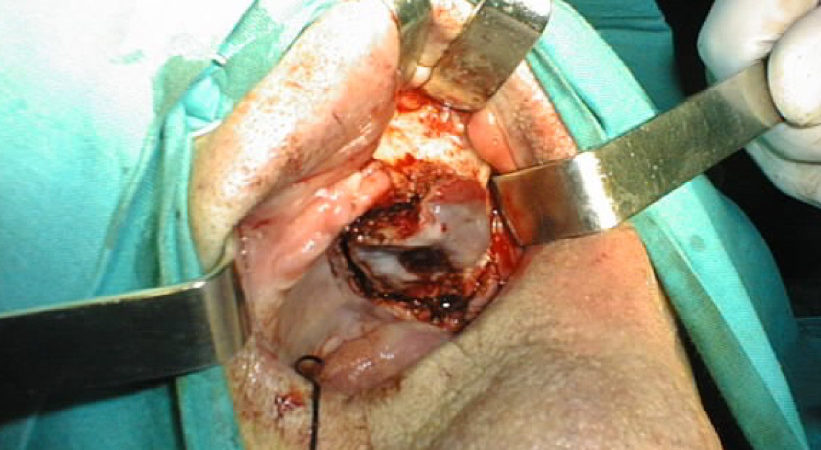

CASO CLINICO N° 3

Paziente di 92 anni portatore di un carcinoma squamoso dell’emipalato duro di sx infiltrante il seno mascellare omolaterale T4N1. È stata effettuata una maxillectomia parziale con dissezione conservativa del collo.